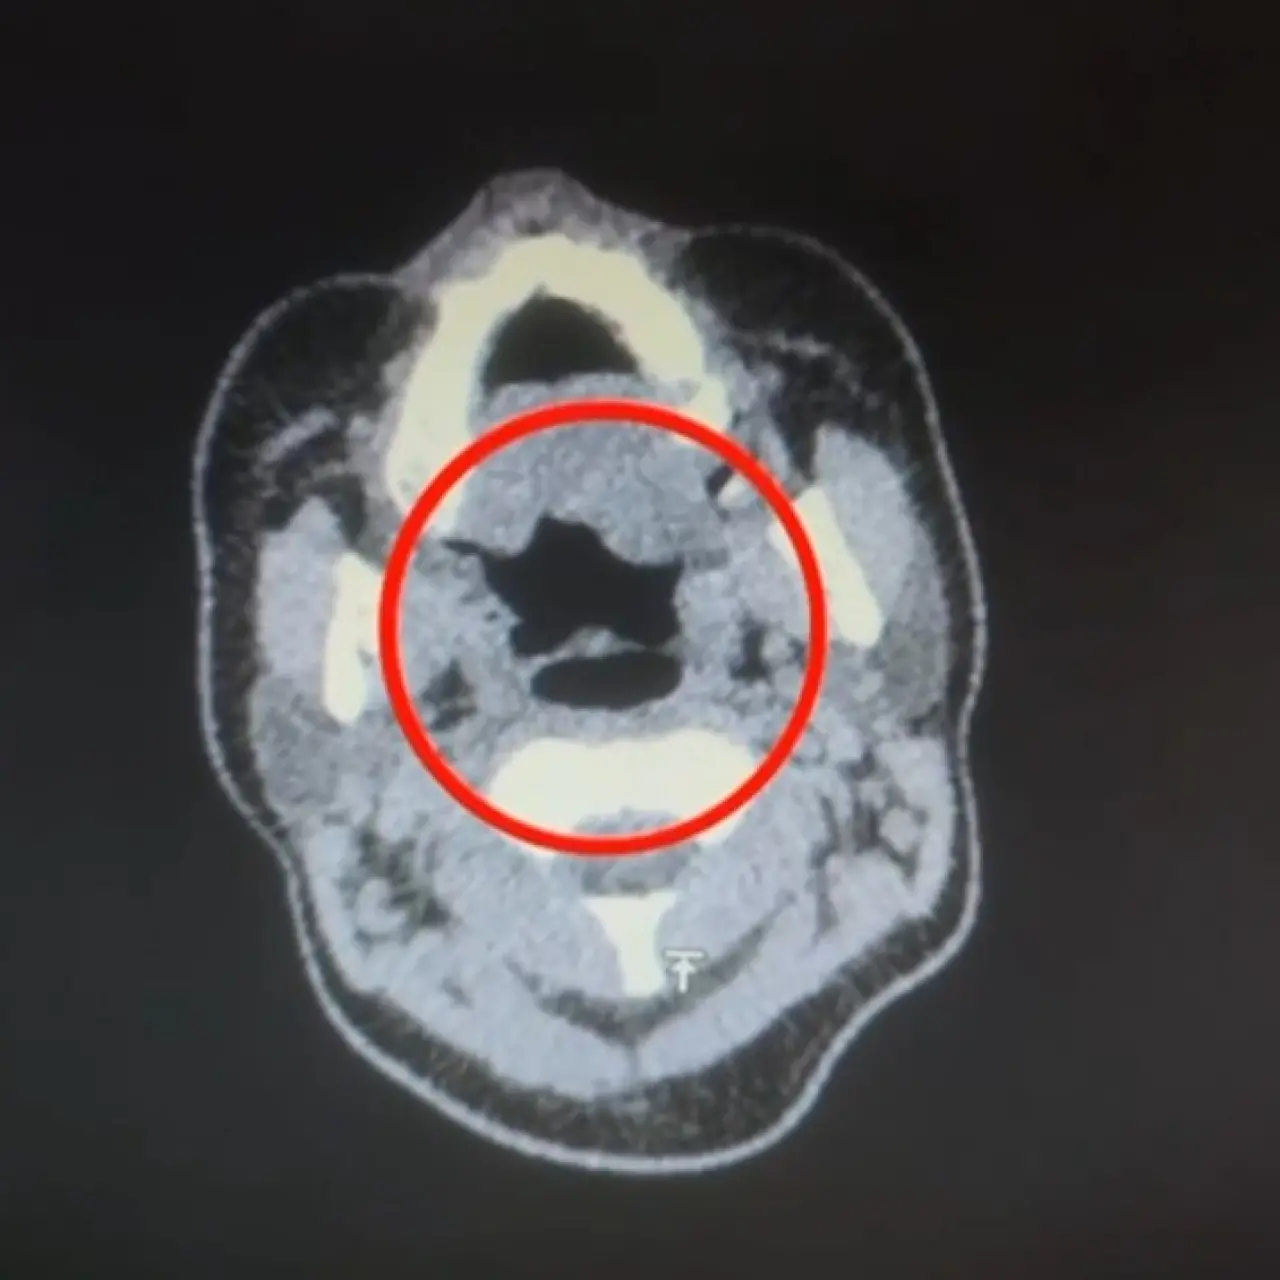

Kayseri İl Emniyet Müdürlüğü Narkotik Suçlarla Mücadele Şube Müdürlüğü ekipleri, uluslararası uyuşturucu madde ticareti yapan kurye şahıslara yönelik operasyon düzenledi. Operasyonda A.R.’yi (27) gözaltına alan ekipler, şahsı hastane muayenesine götürdü.

Gerçekler İç Beden Kontrolüyle Ortaya Çıktı

Şüphelinin yapılan iç beden muayenesinde, mide kısmında bulunduğu tespit edilen 50 adet kapsül şeklinde toplam 500 gram uyuşturucu madde ele geçirildi.

’Uyuşturucu madde ticareti yapmak’ suçundan gözaltına alınan şüpheli emniyete götürüldü.